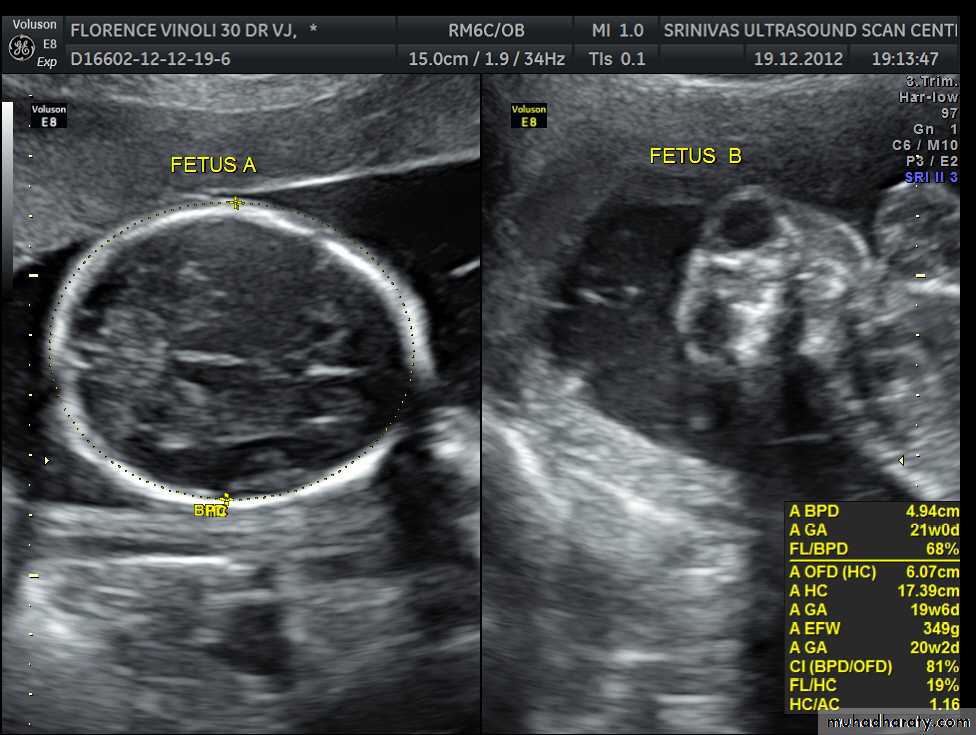

BPD together with head circumference (HC), abdominal circumference (AC), and femur length (FL) are computed to produce an estimate of fetal weight. In the second trimester this may be extrapolated to an estimate of gestational age and an estimated due date (EDD) .